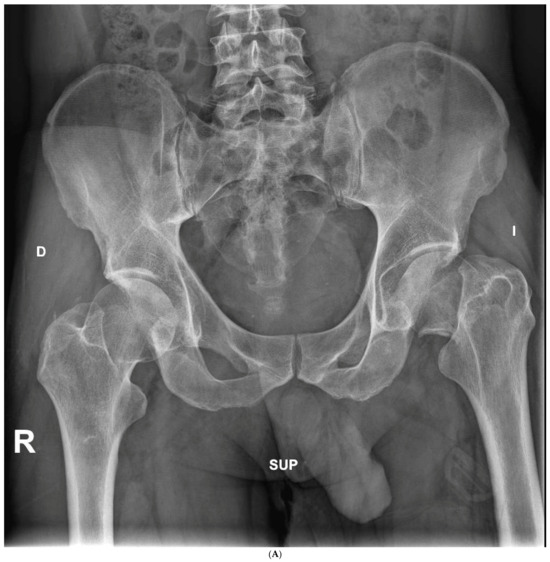

The average cup inclination and anteversion were 43° ± 3° (range, 38–50°) and 10° (range, 0–15°), respectively, in the SFS group, compared with 44° ± 5° (range, 37–50°) and 5° (range, 3–15°) in the CSS group. All acetabular components were positioned within Lewinnek’s safe zone. No radiolucent lines, cup migration, or broken screws were observed in either group throughout the follow-up period. Radiographic signs of osseointegration were present in all implants, with at least three of Moore’s criteria met in every SFS case (Figure 3A–C), indicating complete osseointegration. Similar findings were noted in the CSS group (Figure 4A–C). No femoral radiolucency or periprosthetic osteolysis was detected at any scheduled follow-up. Stem subsidence of approximately 3 mm was observed at the 3-month follow-up in two hips in the SFS group and three hips in the CSS group; however, these cases were not associated with clinical symptoms or functional impairment. No femoral stem loosening was identified during the follow-up period. A leg length discrepancy (LLD) of less than 1 cm was observed in three hips in the SFS group (average, 4 ± 3 mm) and in eight hips in the CSS group (average, 4 ± 5 mm). None of these discrepancies resulted in clinical or functional complaints, and no heterotopic ossification was identified in the radiographic evaluations (Table 4).

Figure 3.

(A) Preoperative anteroposterior X-ray. Left hip sustained a displaced femoral neck fracture. (B) Postoperative anteroposterior X-ray (SFS group). Both the short stem and acetabular cup appear well osseointegrated and stable at final follow-up. (C) Postoperative lateral X-ray (SFS group). The stem is osseointegrated and there is absence of radiolucent lines at bone-implant interface.